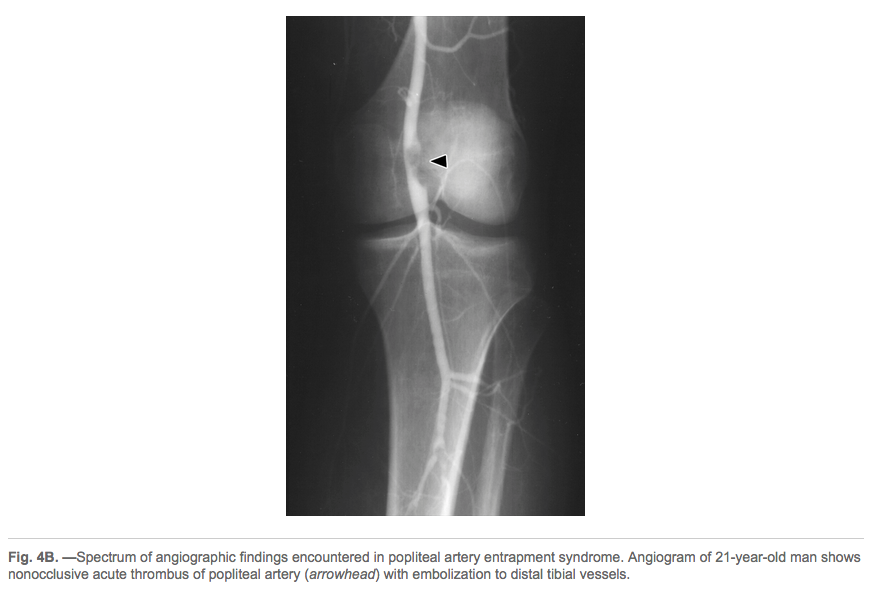

Anatomical abnormalities involving the medial head of gastrocnemius muscle result in popliteal artery entrapment syndrome.

popliteal artery entrapment syndrome